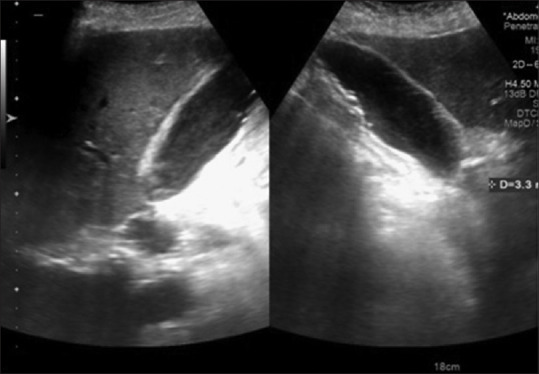

图 9

III b 类病例显示胆囊微结石的超声图像,胆囊壁增厚 3.3 毫米